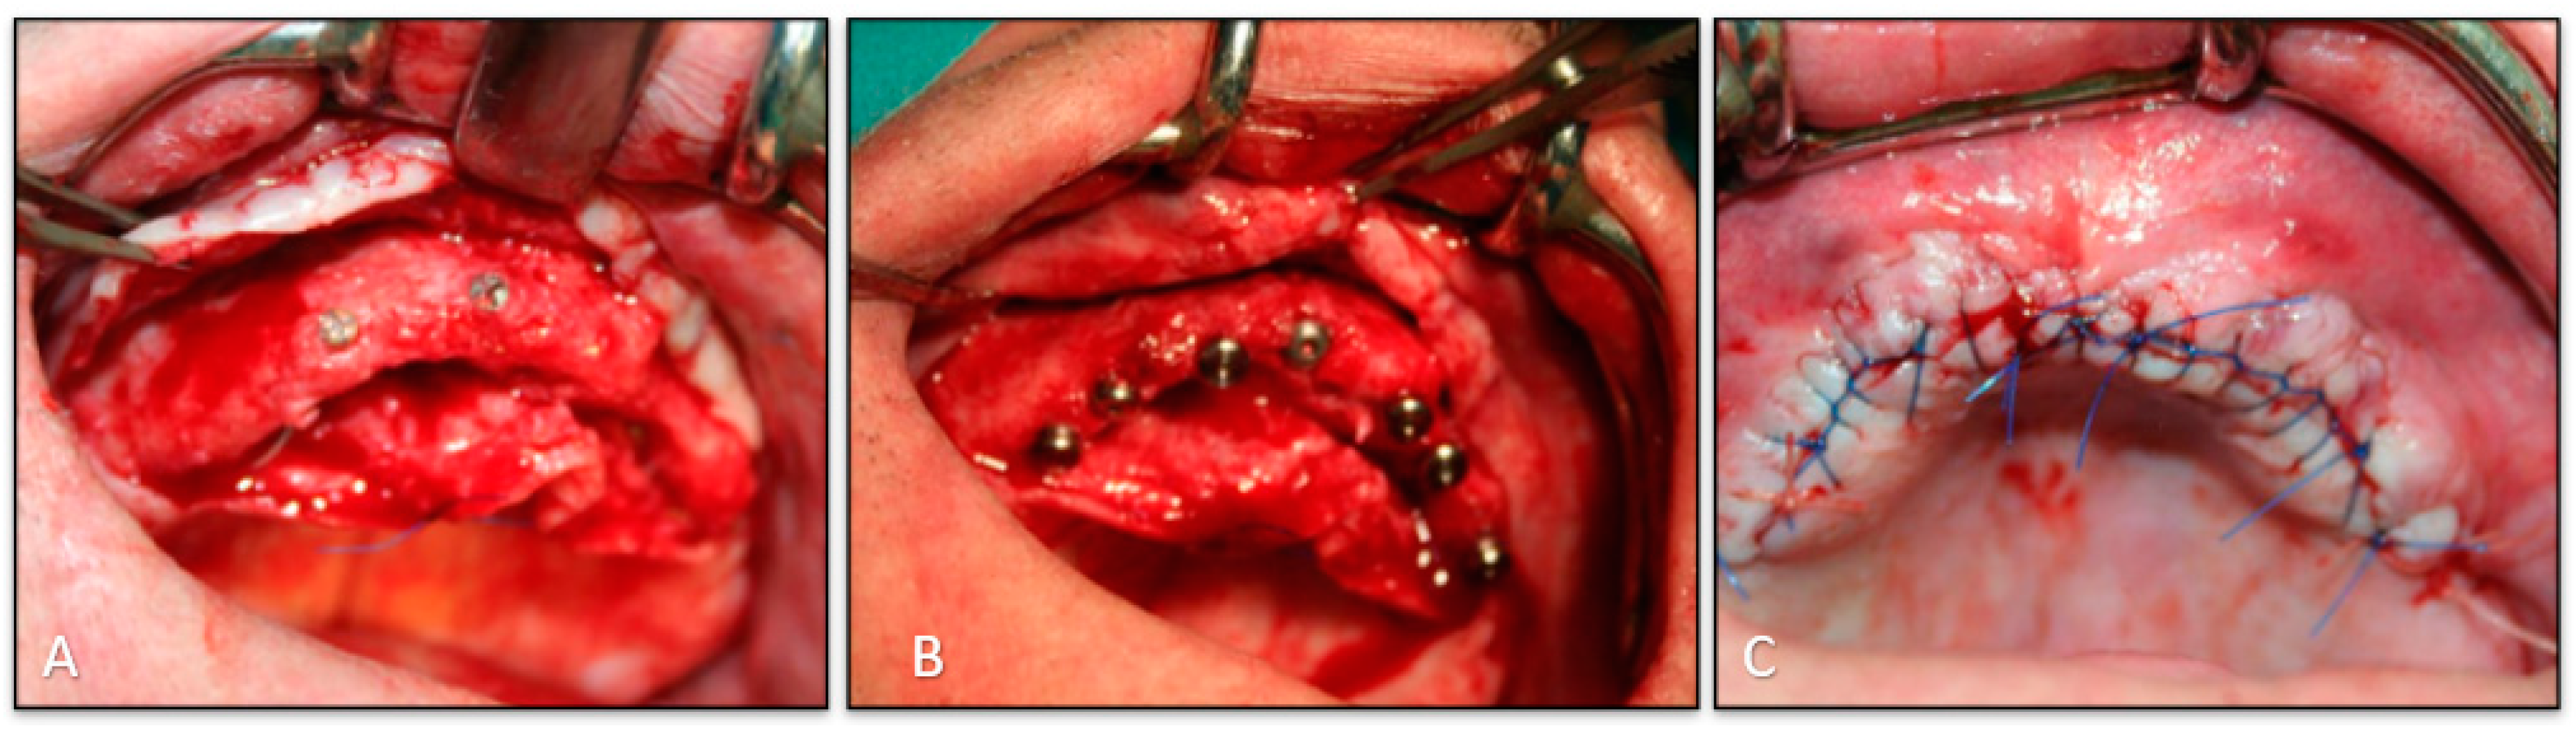

2.2. Surgical Phase